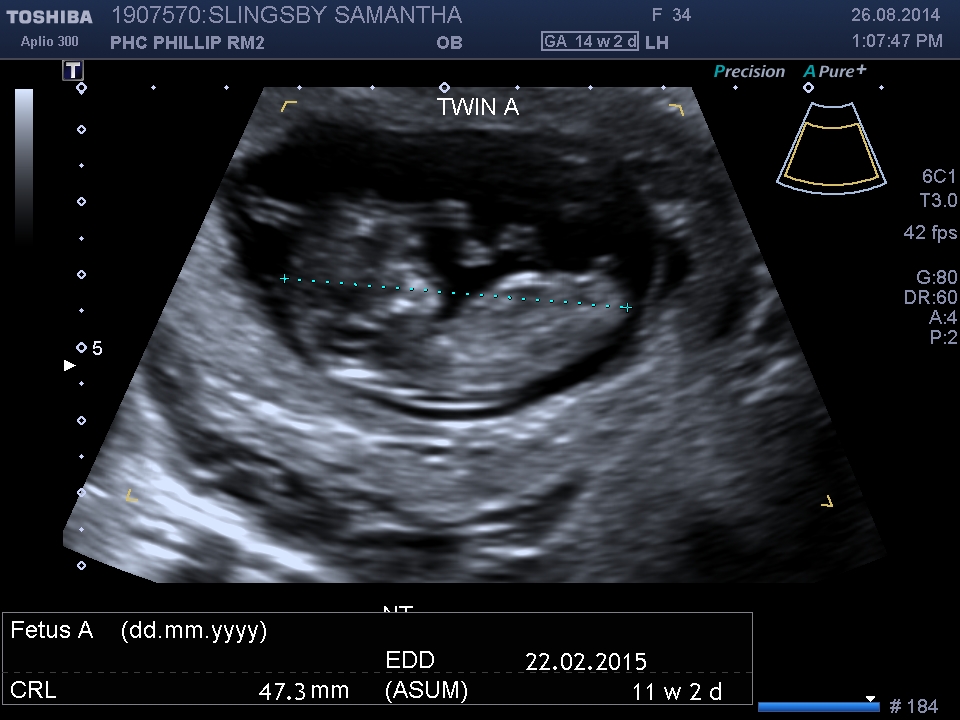

It's 11weeks + 2.